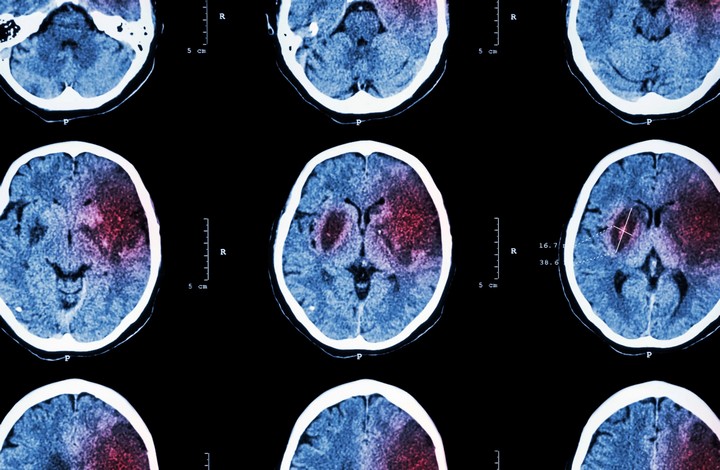

Согласно новому исследованию, введение естественного гормона непосредственно в кишечник снижает когнитивные нарушения, которые возникают в долгосрочной перспективе после инсульта. Эти данные подтверждают растущее число доказательств того, что здоровье кишечника напрямую связано со здоровьем мозга. Ученые надеются, что это исследование откроет путь к новым методам лечения, уменьшающим хронические последствия инсульта.

Инсульт — одно из самых распространенных заболеваний в мире: он случается у каждого четвертого человека старше 25 лет. Хотя острые симптомы инсульта хорошо изучены и поддаются лечению с помощью интенсивной терапии, долгосрочные последствия, такие как когнитивные нарушения и депрессия, сложнее устранить. Исследователи из Техасского университета A&M изучили связь между кишечником и мозгом, чтобы предотвратить долгосрочные повреждения мозга с помощью естественного гормона.

Классические признаки инсульта, такие как ослабление одной стороны тела или нарушение речи, заметны сразу. Но исследователи обнаружили, что уже через несколько минут после инсульта структура кишечника нарушается. Стенка кишечника, которая обычно служит барьером, становится проницаемой. Это позволяет бактериям проникать в другие системы организма, включая мозг, либо вызывать воспаление, усугубляющее последствия инсульта.

В рамках исследования учёные проверили влияние гормона IGF-1 (инсулиноподобный фактор роста-1) на восстановление после инсульта. Его вводили крысам двумя способами: в вену или непосредственно в кишечник. Введение IGF-1 в вену улучшало моторные функции и уменьшало область повреждения мозга в краткосрочной перспективе, но не снижало когнитивные нарушения в долгосрочной. Однако при введении гормона в кишечник наблюдалось значительное улучшение когнитивных функций, хотя острые последствия инсульта не уменьшались.

Исследователи считают, что IGF-1 воздействует на иммунные органы организма, предотвращая дальнейшее повреждение мозга за счёт снижения воспалительных процессов. Это подтверждает, что улучшение здоровья кишечника может оказывать длительное влияние на восстановление после инсульта. В дополнение к работе с IGF-1 учёные изучают трансплантацию здоровых кишечных стволовых клеток в повреждённый кишечник. Это может не только восстановить стенку кишечника, но и снизить объём повреждённых тканей мозга и сохранить когнитивные функции.